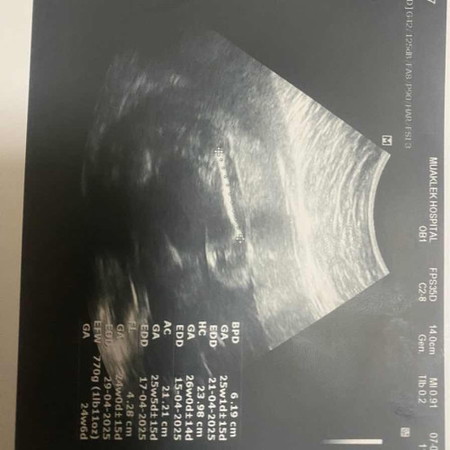

ท้อง 25w คุณหมอบอกน้องน่าจะเป็นผู้หญิงเพราะไม่เห็นไข่